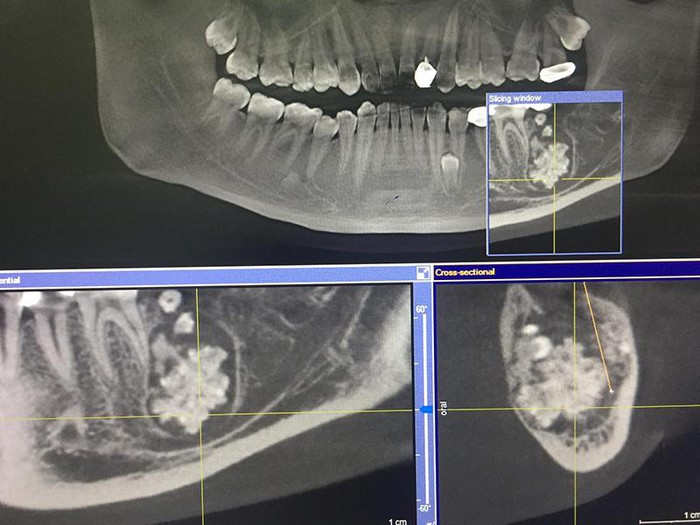

Khi chỉ định chụp X-quang, bác sĩ phát hiện xương hàm dưới có khối u răng kích cỡ 3x4 cm, bên trong chứa nhiều răng to, nhỏ có đầy đủ tổ chức như rằng bình thường, kết lại thành một khối.

| Khối u răng của nam bệnh nhân chứa đầy răng to, nhỏ phía trong. |

BS Đinh Thanh Tùng, khoa Răng Hàm Mặt cho biết, ca phẫu thuật kéo dài hơn 1 tiếng. Do khối u răng nằm sâu, chiếm gần hết thân xương hàm, bám dính chắc vào xương hàm nên bác sĩ phải dùng dụng cụ bóc tách, cắt nhỏ từng phần để lấy ra, tránh tổn thương dây thần kinh.